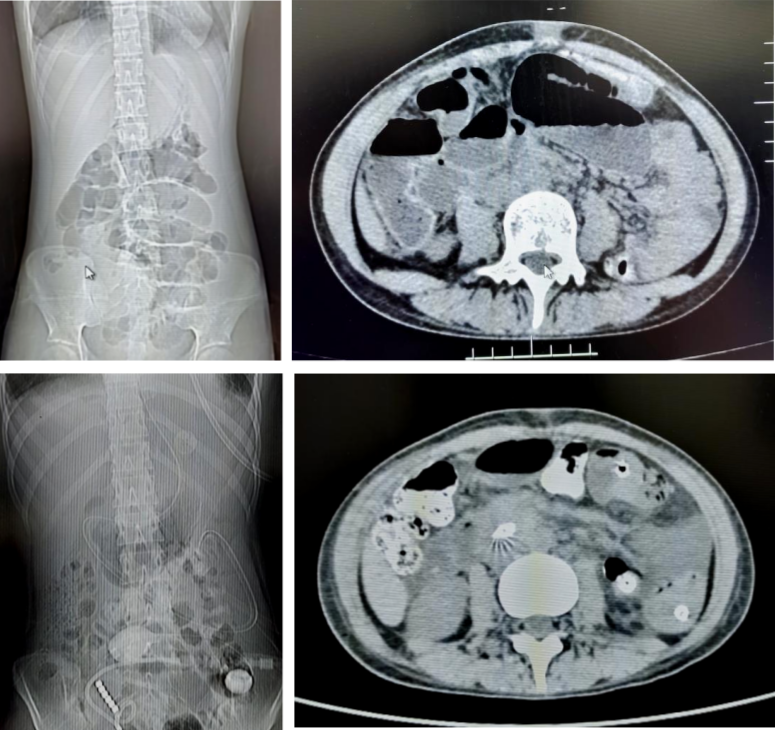

71岁的患者刘先生,因行膀胱癌根治术、回肠代膀胱术出现肠梗阻。后在我院放射介入室行DSA引导下经鼻肠梗阻导管置入术,术后当日患者腹胀较前明显缓解,术后第6天患者排气、排便,肠管恢复通畅,拔除肠梗阻导管。

18岁的患者叶女士,因行阑尾穿孔导致盆腔脓肿后出现肠梗阻。后在我院放射介入室行DSA引导下经鼻肠梗阻导管置入术,术后当日患者腹胀较前明显缓解,术后第3天患者排气、排便,肠管恢复通畅,拔除肠梗阻导管。